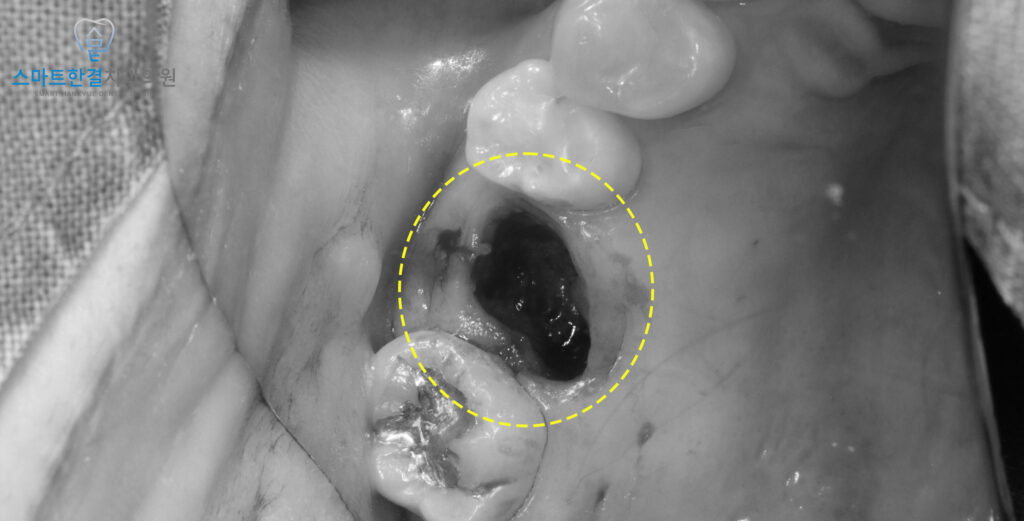

발치를 진행한 모습이예요 ^^

치아 뿌리 끝에 염증이

오래 자리 잡고 있었기 때문에

발치 과정에서 치아와 분리되어,

발치와 바닥에는 염증 조직이

그대로 남아 있는 상태였어요.

이러한 염증은 남겨두면

재발의 원인이 될 수 있으므로,

소파를 통해 염증 조직을

꼼꼼하게 긁어내는 과정이 필요해요.

발치와 내부를 깨끗하게 정리해야만

새로운 뼈가 건강하게 차오르며

양호한 치유가 이루어질 수 있기 때문이랍니다.